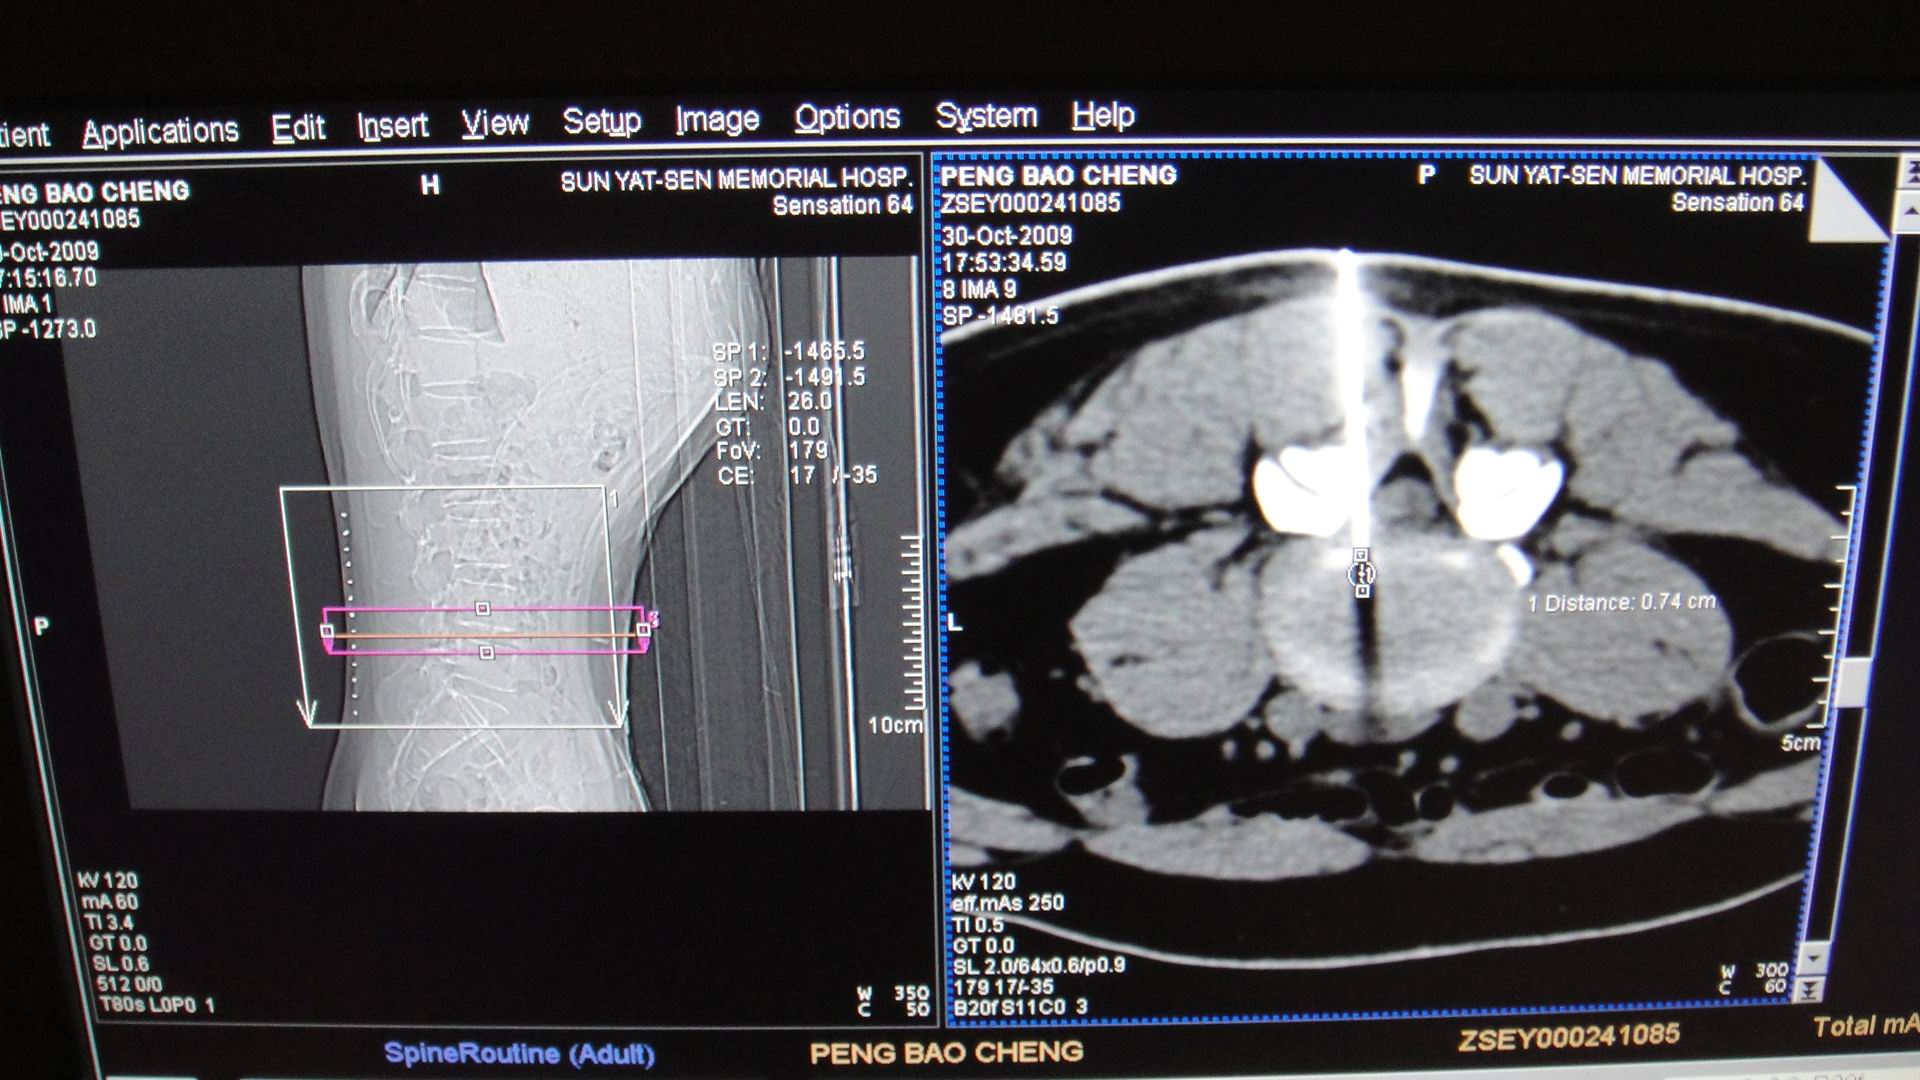

CT引导射频靶点热凝术

射频靶点热凝术

CT精确定位